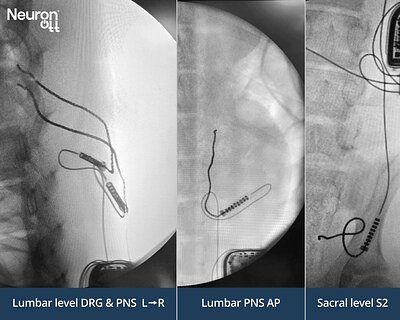

- 3 nerve targets: Neuronoff's Injectrode successfully stimulated the Lumbar Dorsal Root Ganglion, Lumbar Dorsal Ramus, and Sacral S2 foramen using a single IPG.

In the recent study, Neuronoff demonstrated this capability by placing tripolar Injectrodes at three separate, anatomically distinct sites routinely targeted by pain physicians: the Lumbar Dorsal Root Ganglion (DRG), the Lumbar Dorsal Ramus, and the Sacral S2 foramen. Using a single, remotely controlled IPG, the company proved it could independently and selectively stimulate each target. This multi-channel capability from a single power source is a critical step in showing the platform's versatility.